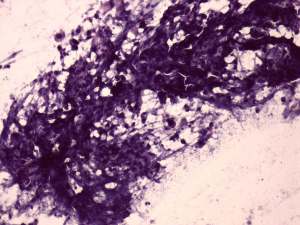

Cytology from the lymph node resulted in metastatic squamous cell carcinoma.

Histopathology disclosed a lymph node metastasis of a basaloid squamous cell carcinoma. The tumor did not spread extracapsular and was HPV-positive. Only one of the 18 removed node contained metastasis.